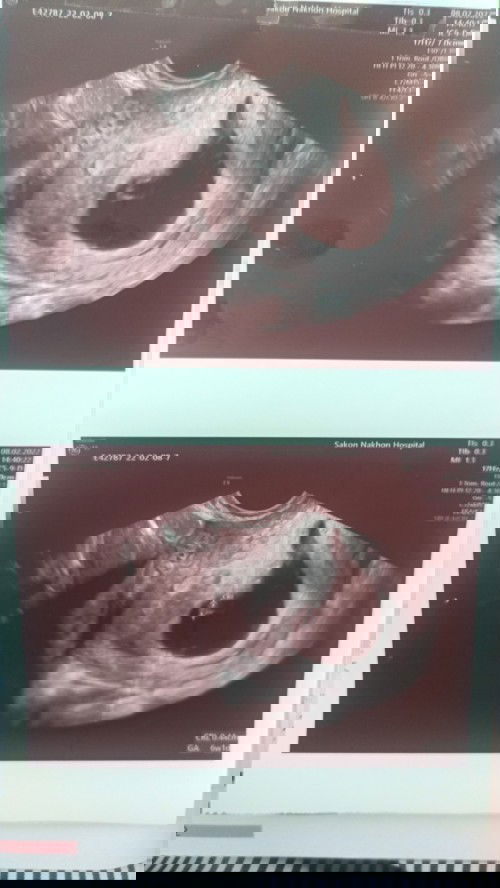

เมื่อวานหมอนัดครบ 10wk+1 จากผลอัลตราซาวด์หมอบอกว่าน้องไม่โต ตัวน้องเริ่มฟ่อแล้ว คุณหมอขอยุติการตั้งครรภ์ไว้แค่นี้ หมอให้แอดมิทเลย #เราขอเลื่อนการแอดมิท 😭เราทำได้แค่ร้องไห้ทำอะไรไม่ถูกพูดไม่ออก และเราเลือกไม่ยอมเอาลูกออก เรายังคิดว่าสักวันนึงเราก็ยังมีความหวังลูกเราต้องอยู่กับเรา #ลูกคนแรก #เฝ้ารอน้องมา4ปี😭 #ขอกำลังหน่อยค่ะแม่ๆ😭